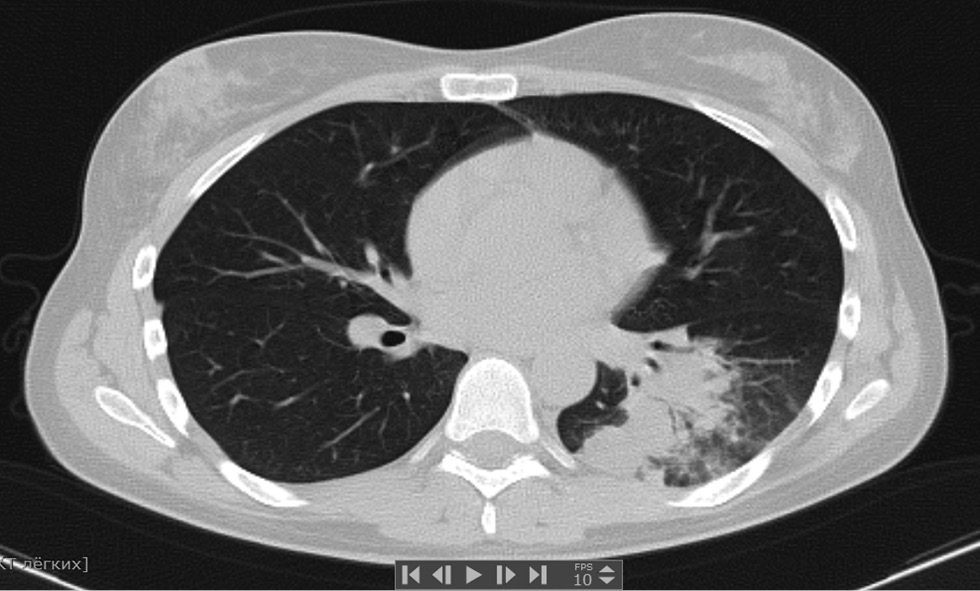

Patient M., 50 years old, was admitted to the St. Petersburg Clinical Hospital of the Russian Academy of Sciences on 06/07/2020 with a referral diagnosis of bilateral ovarian tumors. Ovarian cancer was questionable. Lymphadenopathy. Adenomyosis. Myoma of the uterus. Condition after viral community-acquired pneumonia caused by the SARS-CoV-2 virus in April 2020 (lung damage according to computed tomography data ~ 40%) (Fig. 1, 2).

Fig. 2. Computed tomography of the lungs, June 2020, upon admission (picture of fibrotic changes in the lung after viral pneumonia caused by the SARS-CoV-2 virus)